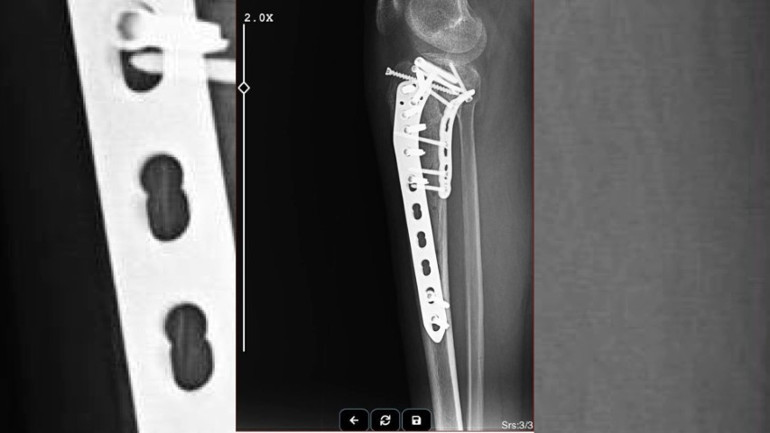

Ağır yaralanarak ambulansla hastaneye kaldırılan Avukat Teksöğüt, ilki Şanlıurfa’da olmak üzere 3 ameliyat geçirdi. Fizik tedavi süreci devam eden Teksöğüt, Ahmet E.'den şikayetçi oldu. Ahmet E. 28 Şubat'ta Şanlıurfa'da hakim karşısına çıkacak.

Avukat Büşra Teksöğüt "Geçen yıl Ocak ayında kesinleşmiş bir alacağımı tahsil amacıyla Urfa’nın Suruç ilçesine gittim. İşlemlerimi tamamladım. Daha sonra dönüş yolunda takip edildim. Takip edildiğimi saldırdıktan sonra öğrendim. Ağır şekilde yaralandım, hastaneye kaldırıldım. Haciz işlemleri için gittiğim borçlu tarafından saldırıya uğradım. 2,5 aylık bir hastane sürecim, aylarca evde yatış sürecim oldu. 3 ameliyat geçirdim. Ameliyatlarım hala devam ediyor. Bacağımda platinler mevcut, kaybettiğim belli başlı dokular oldu. Bu süreç psikolojik olarak tabii ki beni çok etkiledi. Sağlık problemlerim hala devam ediyor, tedavi sürecim hala devam ediyor. Burada asıl olay, yapılan saldırının mesleğe karşı, bir avukata ve bir kadına yapılmış olmasıydı" dedi.